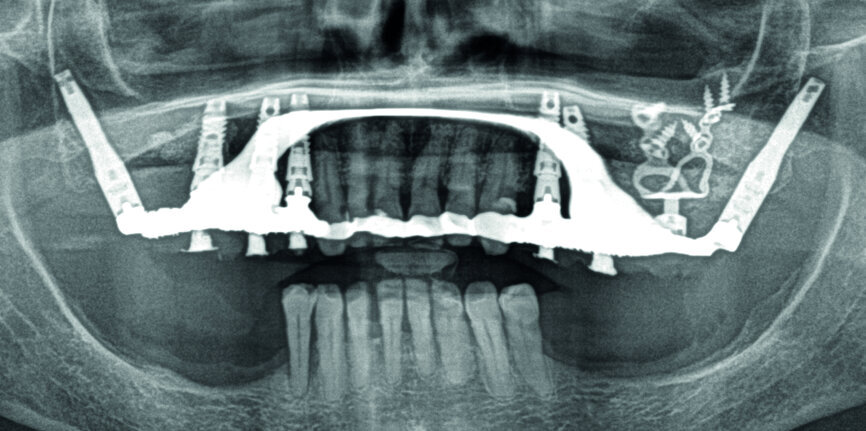

Figs. 8a et b : Contrôles radiologiques du bon ajustement des armatures après vissage.

Pose du bridge :

Après l’essayage en bouche, facilité par la passivité, régler l’occlusion, vérifier l’esthétique et la phonation, puis répartir le vissage manuel (vis or M1.4). Enfin, contrôler radiologiquement le bon ajustage de l’armature (Figs. 8a–b). À 24 h, resserrer manuellement les vis à 10 N/cm, fouler une boulette de téflon dans le puit de chaque vis et le recouvrir à l’aide d’un composite.